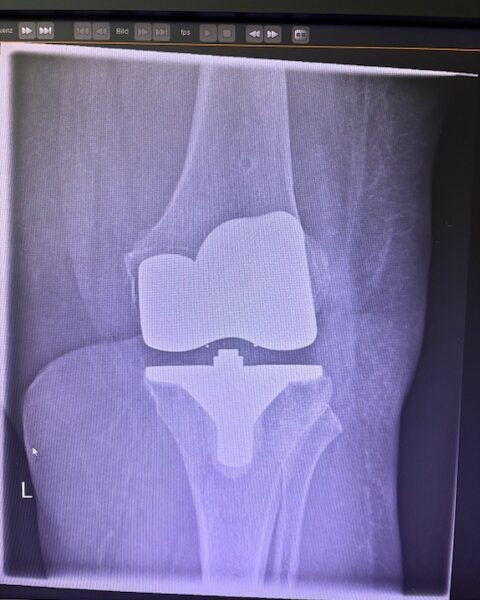

Τα εμφυτεύματα που χρησιμοποιήθηκαν στο γόνατο της ασθενούς είναι της Aesculap: E-Motion Pro, μηριαίο μέγεθος 4, κνημιαίο μέγεθος 4, με ενθέμα (inlay) 10mm.

Η επέμβαση ολοκληρώθηκε χωρίς επιπλοκές, με ελάχιστη απώλεια αίματος και ταχεία κινητοποίηση της ασθενούς.